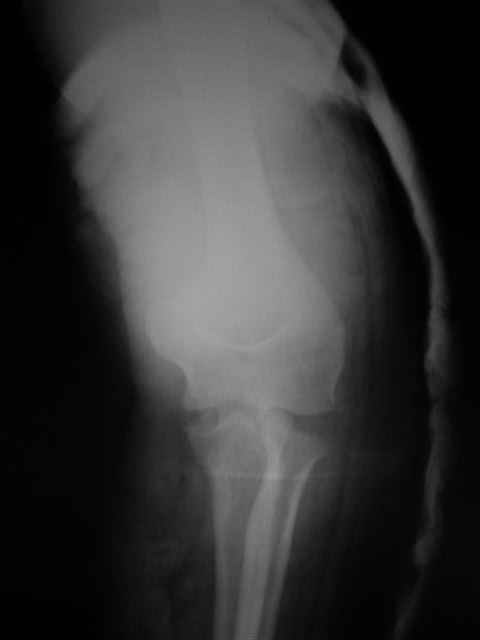

Вывих костей предплечья и перелом головки лучевой кости. |

Уважаемые коллеги!Помогите с источниками литературы по вопросу о сроках резекции головки лучевой кости и гетеротопической оссификации после вывиха костей предплечья. Необходимо ответить на жалобу, где больная просит возместитьматериальные затраты на лечения с лечащих врачей, которые участвовали влечении с 4.09.04 по 10.11.04, объясняет, что врачи нарушили стандарты леченияи поздно направили на оперативное лечение.История болезни, женщина 46 лет упала дома 4.09.04, получила заднелатеральныйвывих костей предплечья и перелом головки лучевой кости, под местной анестезиейвывих вправлен, на контрольной рентгенограмме соотношение отломков головкилучевой кости расценено, как удовлетворительное. Наложена задняя гипсовая шина.Лечение: холод, кетанов 3 дня, магнитотерапия, ЛФК пальцев, рентген контрольчерез 7 дней, с 8.09.05 наклофен 50 мг 2 раза в день. 11.09.04 на контрольной рентгенограмме состояние отломков прежнее. 30.09.04. Гипсовая шина снята через 26 дней. Лечение: ЛФК, массаж, электрофорезлидазой.9.10.04. В левом локтевом суставе сгибание 80, разгибание 120.19.10.04. Сгибание 80, разгибание 140, ротационные движения в пределах 10 гр.28.10.04. Сгибание 80, разгибание 150, ротационные движения в пределах 10 гр.10.11.04. На рентгенограмме локтевого сустава отмечается гетеротопическаяоссификация.Учитывая неэффективность консервативного лечения, больная направлена на оперативноелечение.Больная по собственным каналам уехала в г. Киев, где произведенарезекция головки лучевой кости, после операции развился неврит лучевого нерва.На данный момент больная продолжает лечение у нейрохирурга.-- С уважением,Анатолий Борзунов

А есть снимки?

Во время встречи фотоаппарата не было, забрать снимки на время, муж больной снимки не разрешил.